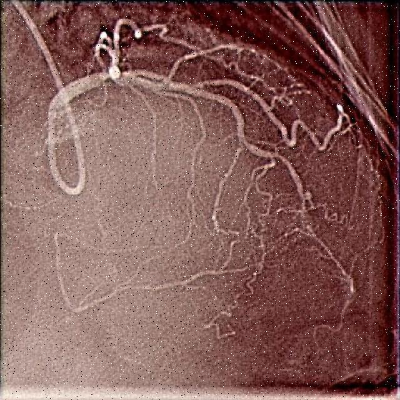

心血管造影图像具有独特的视觉特征,这些特征对目标检测算法提出了特殊挑战:

血管结构的复杂性使得传统检测方法难以准确识别。血管的直径从几毫米到几毫米不等,且常常与周围组织交织在一起。低对比度问题使得血管边界难以辨认,特别是在血管狭窄或闭塞区域。噪声的存在进一步增加了检测难度,特别是在低剂量X射线成像条件下。这些特点要求我们的检测算法必须具备强大的特征提取能力和鲁棒性。🏥

为了更直观地展示模型性能,我们可视化了一些检测示例。从图中可以看出,YOLO11-CSFCN能够准确检测出各种形态的血管,包括细小分支、交叉区域和狭窄部分。即使在低对比度区域,模型也能保持较高的检测精度。这与通道-空间注意力机制密切相关,它使网络能够聚焦于血管特征,抑制背景噪声。📈